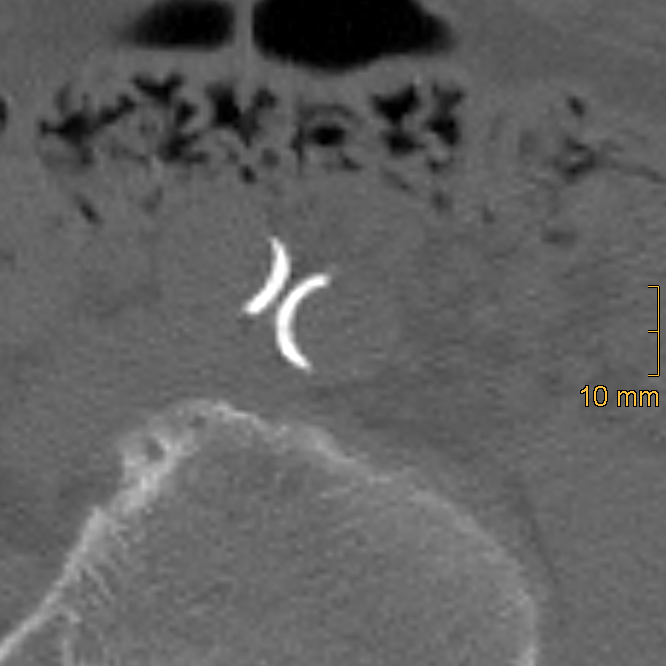

Iliac calcification was assessed using a semi-quantitative method described by Davis et al. [26]. Both common iliac arteries (CIA) and external iliac arteries (EIA) were evaluated bilaterally using standard bone window settings (window width = 2500 HU; window level = 300 HU). The CIA was defined from the aortic bifurcation to the iliac bifurcation, and the EIA from the iliac bifurcation to the level of the superior aspect of the femoral head. Each vessel segment was scored in three domains: morphology (0–3), circumference (0–4), and length of involvement (0–4). To ensure accurate assessment, multiplanar reformations were generated to correct for vessel tortuosity and to obtain orthogonal cross-sectional views, which is essential for the evaluation of calcification morphology and circumferential extent, whereas the longitudinal extent of calcification was assessed on standard axial images. Morphology was graded as follows: 0 = no calcifications, 1 = thin linear (≤1 mm), 2 = thick linear (>1 mm), 3 = bulky (>2 mm, convex luminal margins). Representative examples of morphologic grading are shown in Figure 2, Figure 3 and Figure 4. Circumference and length of involvement were scored as 0 = no calcifications, 1 = 1–25%, 2 = 26–50%, 3 = 51–75%, 4 = 76–100%. The highest score per segment was used in cases of multiple calcified regions. For each patient, bilateral scores were summed and averaged, resulting in the common iliac artery calcification score (CIACS) and the external iliac artery calcification score (EIACS). Both scores were subsequently combined to generate the total iliac artery calcification score (TIACS). Severity was classified as follows: 0–3.75 = none to mild, 4–7.75 = moderate, 8–11 = severe.

Figure 3.

Example of thick linear calcification in the left common iliac artery, corresponding to a morphology score of 2. An additional thick linear calcification is also visible in the right common iliac artery.